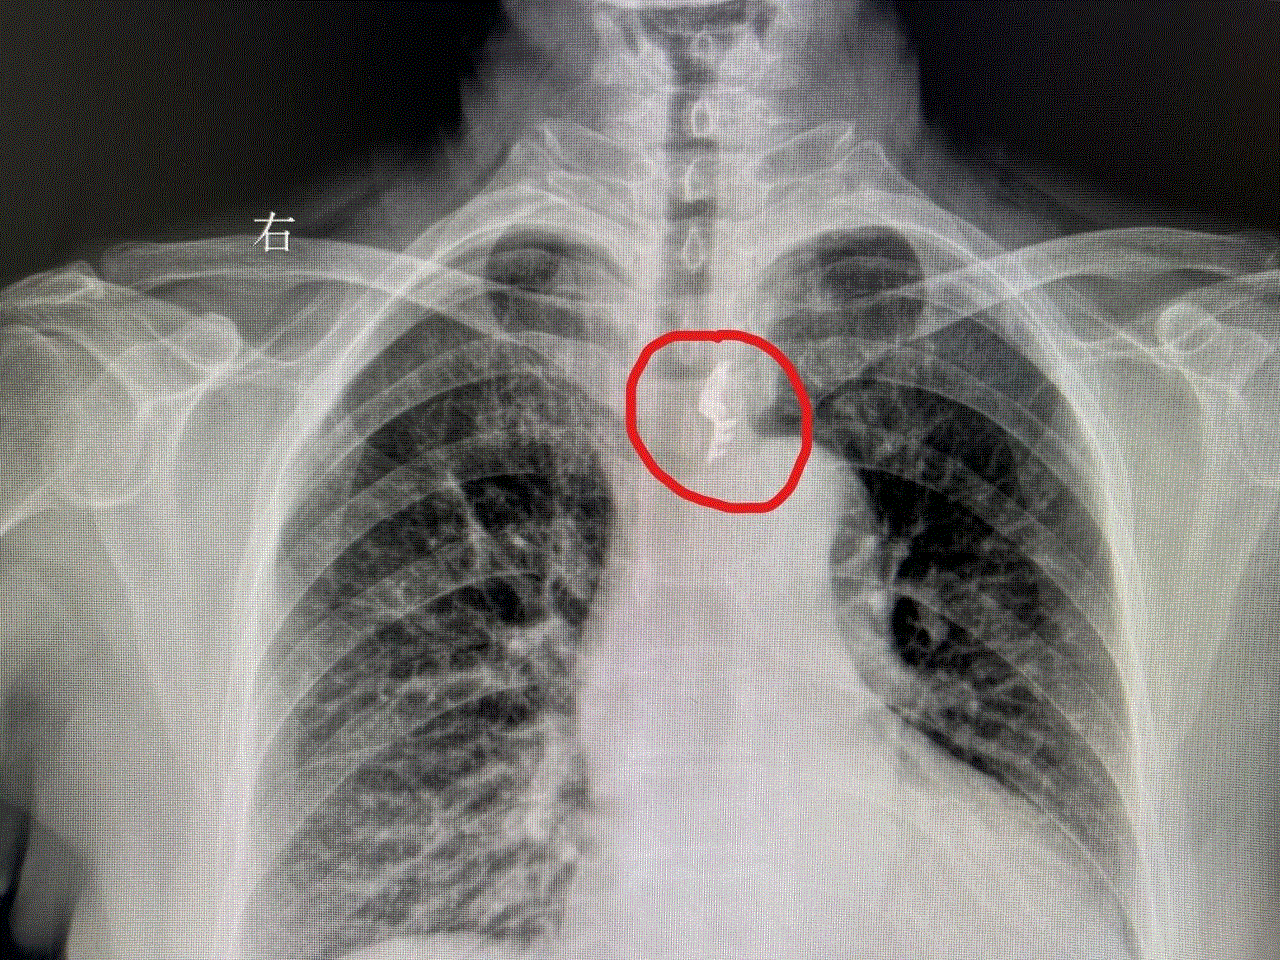

经了解,原来是70岁的赵阿姨误吞了假牙,胸片显示假牙在食道上段滞留。因为假牙可能会有挂钩等尖锐金属,所以食道随时都有被刺穿的危机,取出假牙刻不容缓!

经测量,假牙竟然有3cm长,并且一端带有金属挂钩,万幸地是被及时取出并未刺穿食道。